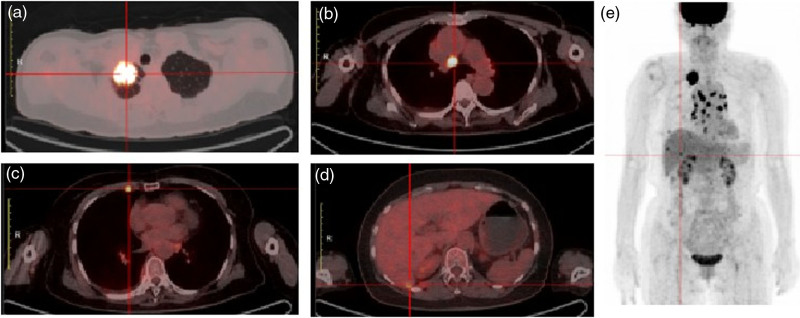

Almonertinib, a representative epidermal growth factor receptor tyrosine kinase inhibitor (EGFR-TKI), is the first-line standard treatment for EGFR-mutant advanced non-small-cell lung cancer; however, it may induce drug-related interstitial lung disease (ILD). This case report presents a 67-year-old female with advanced lung adenocarcinoma, who was diagnosed with an EGFR exon 19 deletion mutation. After 2 months of first-line almonertinib treatment (110 mg/day), a PR was achieved; however, progressive respiratory distress emerged. Chest computed tomography revealed ground-glass opacities accompanied by grid-like changes in both lungs, leading to a diagnosis of EGFR-TKI-related ILD (grade 2). Following glucocorticoid treatment and medication discontinuation, the lung lesions improved. Given the persistent tumor activity, the patient was switched to firmonertinib (80 mg/day) for targeted therapy. This switch did not lead to a recurrence of ILD symptoms, with a progression-free survival exceeding 5 months and good tolerability. This suggests that for patients with ILD associated with almonertinib and firmonertinib may serve as an effective and safe alternative. Closely monitoring ILD in clinical practice and promptly switching to similar drugs may avoid chemotherapy intervention and optimize treatment strategies. This case marks the first report of clinical experience achieving sustained remission by switching to a similar drug, firmonertinib, in patients with ILD related to almonertinib.

Abstract Image